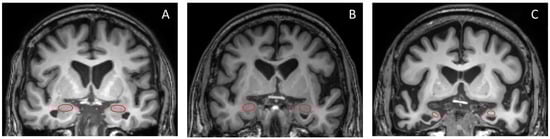

Overall, the ROC curve analysis identified the left amygdala/ICV ratio as the parameter demonstrating the most significant alterations across all compared groups, yielding high sensitivity and specificity for diagnosis. Figure 6 displays the coronal section pictures from T1W MRI of (A) NC, (B) MCI, and (C) dementia subjects in the study. The red circles represent the amygdala, which exhibits prominent size differences between all studied groups [30]. However, in real-world clinical practice, it can be quite challenging for radiologists to visually assess and quantify the degree of amygdala shrinkage.

Figure 6. Coronal T1W brain MR images of (A) NC, (B) MCI, and (C) dementia subjects are presented in this study. The red circle highlights the amygdala.